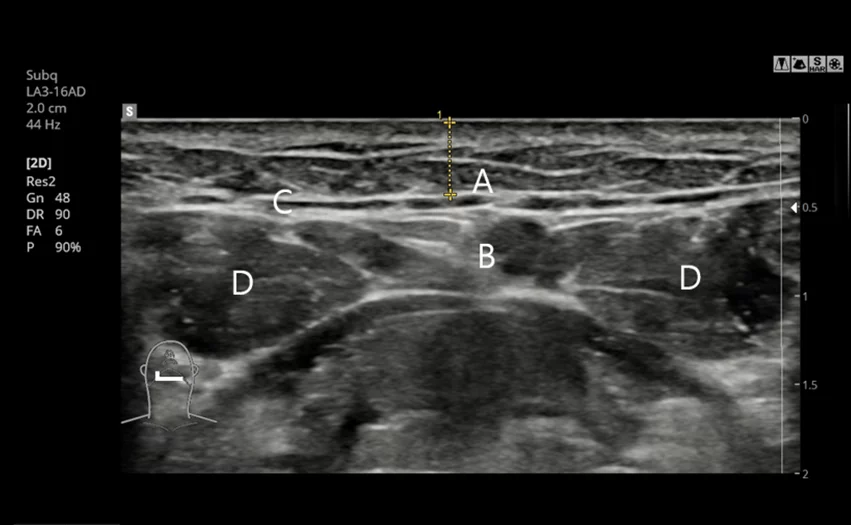

5. Chẩn đoán cá nhân hóa trước phẫu thuật bằng CT và siêu âm

Vị trí và kích thước của tuyến nước bọt được phân tích chính xác thông qua chụp CT và siêu âm. Khi cần, phẫu thuật loại bỏ tuyến nước bọt sẽ được tiến hành theo phương pháp tinh tế và phù hợp từng trường hợp.